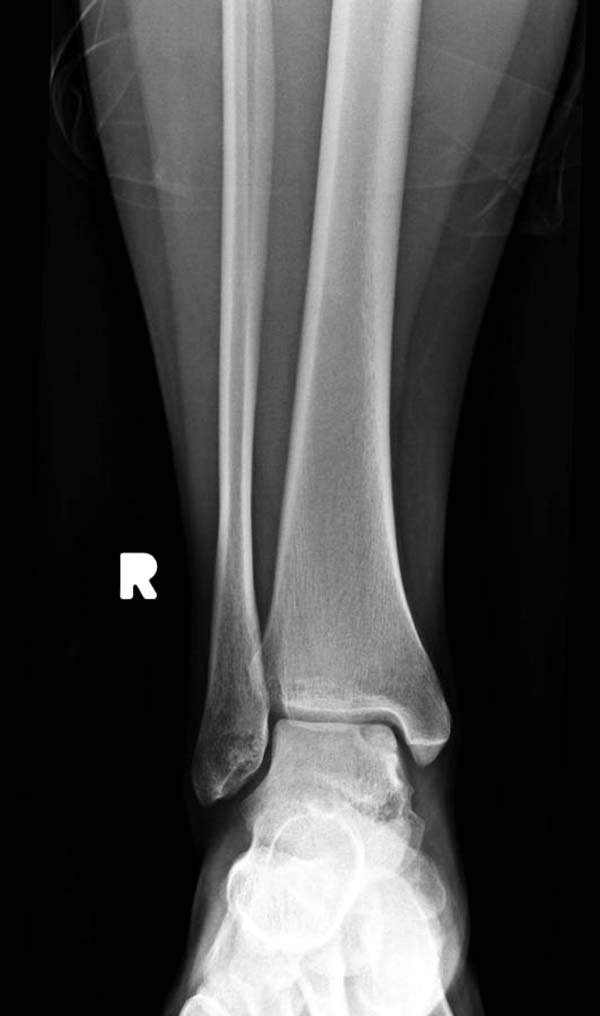

Разбираемый случай не имеет ничего общего с классическим Аваскулярным Некрозом Таранной кости. Здесь так назывемый (osteochondral defect) или osteochondritis dissecans (OCD) таранной кости, при котором патология локализуется в медиально-верхнем нагрузочном отделе. В основном OCD

встречается после хронической травмы, но бывают случаи врожденного генеза, которые обнаруживаются при случайных исследованиях.

Симптоматология  OCD выражается слабым отеком, а более сильные боли наступают после физической нагрузки. В отличие от АВН тарана, когда боли постоянные, а при OCD боли изчезают после отдыха. В начальных стадиях

на рентгенограммах не всегда заметны склерозные участки, и поэтому в большинстве диагноз устанавливается поздно. Приход КТ и МРТ улучшил диагностику, и в срезах внутри кисты можно увидеть жидкость, но это не означает проявление симптоматологии. Симптомы проявляются с момента образования внутрисуставных краевых фрагментаций!

Имя     : 1 OCD ap 1.jpg

Тип     : image/jpg

Размер  : 44094 байтов

Описание: отсутствует

Url     : http://weborto.net:8080/pipermail/ortho/attachments/20120408/bb356219/attachment-0012.jpg